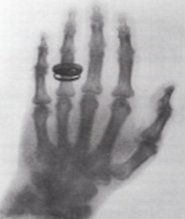

倫琴的X-Ray照片